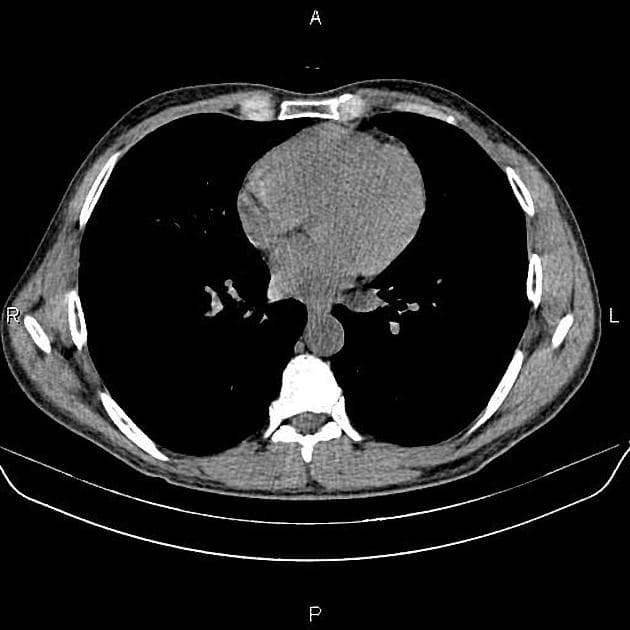

- Có giãn dạng thoi các ống mật ngoài gan (bao gồm ống mật chủ và ống gan chung) chứa nhiều ổ giảm tín hiệu trên mọi chuỗi xung, phân bố theo trọng lực, phù hợp với hình ảnh sỏi.

- Không có giãn đường mật trong gan.

Interpretation: U nang ống mật chủ (type 1) kèm theo tổn thương IPMN nhánh bên phát hiện tình cờ (incidental side branch IPMN).

U nang ống mật chủ - type I (choledochal cyst - type I)